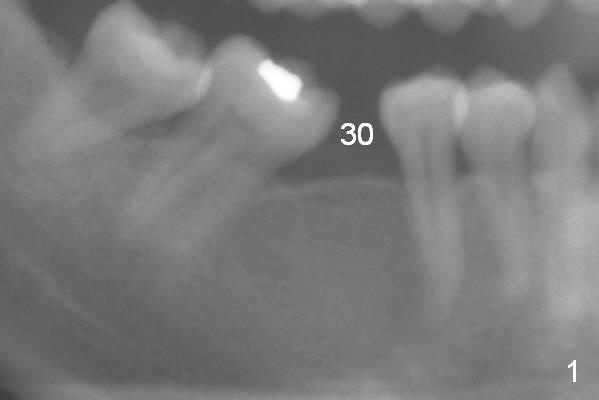

Six months of orthodontic uprighting (including open coil spring, Omega loop and lingual buttons), there seems to be enough space to place an implant at #30 with new bone formation mesial to #31 and distal to #29 (Fig.2,3 arrowheads). The center of resistance (for rotation) is at the furca (Fig.2 O). The void (*) created with upright is going to be filled.

A provisional is fabricated 1 month postop to prevent the tooth #31 from rotation under the tension of the open coil spring, as mentioned above. Acrylic is added distal for #31 distalization nearly 2 months postop. More definitive orthodontic action begins 3 months postop (Fig.7, banding and open coil spring). The edentulous space increases to satisfactory width 3.5 months postop (Fig.8). A normal sized crown is delivered 4 months postop (Fig.9). The patient is pleased with the new tooth (Fig.10 nearly 6 months post cementation). There is no bone loss 13 months post cementation (Fig.11 (pan), 12 (CT coronal section (L: lingual))).